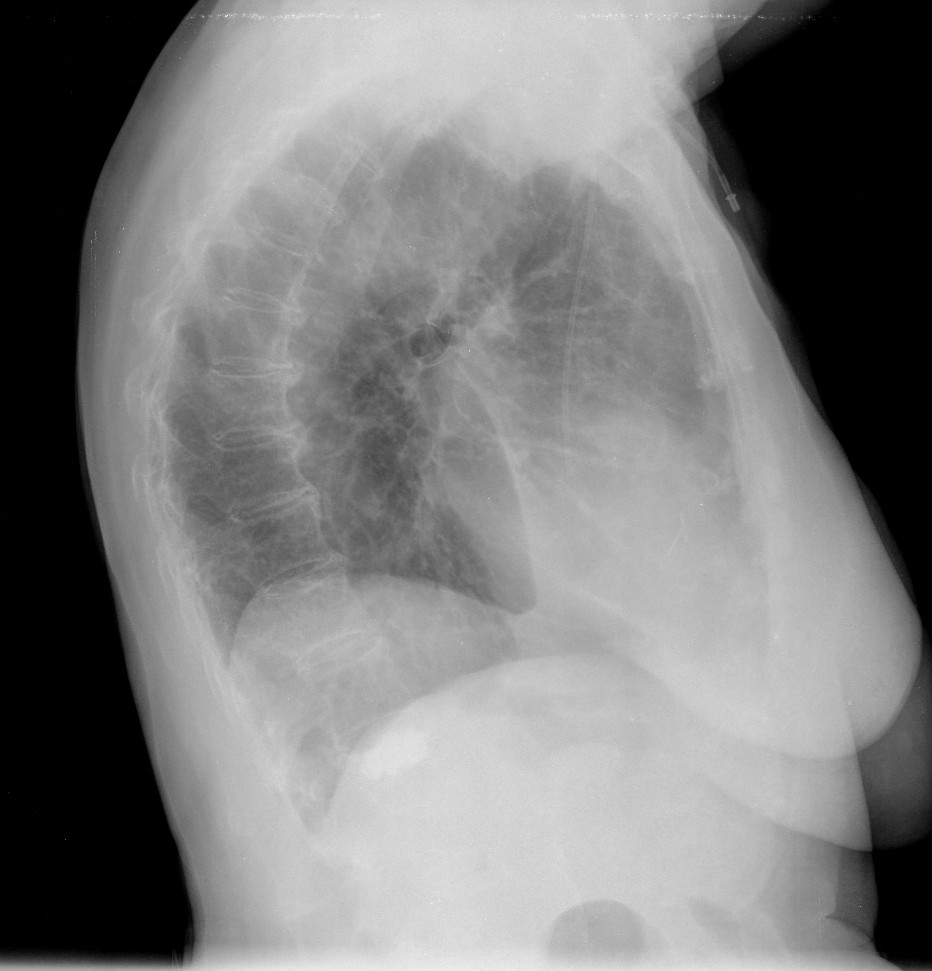

CASO: Febrícula y tos de 4 días de evolución.

Hallazgos:

- En la placa PA se observa una asimetría en los hilios pulmonares, el hilio izquierdo tiene una densidad aumentada.

- Tras examinar la placa lateral se observa un aumento de densidad en la columna que puede ser compatible con una condensación, es el signo de la desnificación vertebral.

SIGNO DE LA DENSIFICACIÓN VERTEBRAL: En la radiografía lateral normal, la densidad de la columna torácica tiende a disminuir desde la parte superior hasta el diafragma; la alteración de ese patrón por la presencia de una densidad superpuesta a la columna, indica la existencia de una consolidación pulmonar. Este signo adquiere especial valor cuando en la proyección posteroanterior la consolidación está oculta en el espacio retrocardíaco o en la base pulmonar.